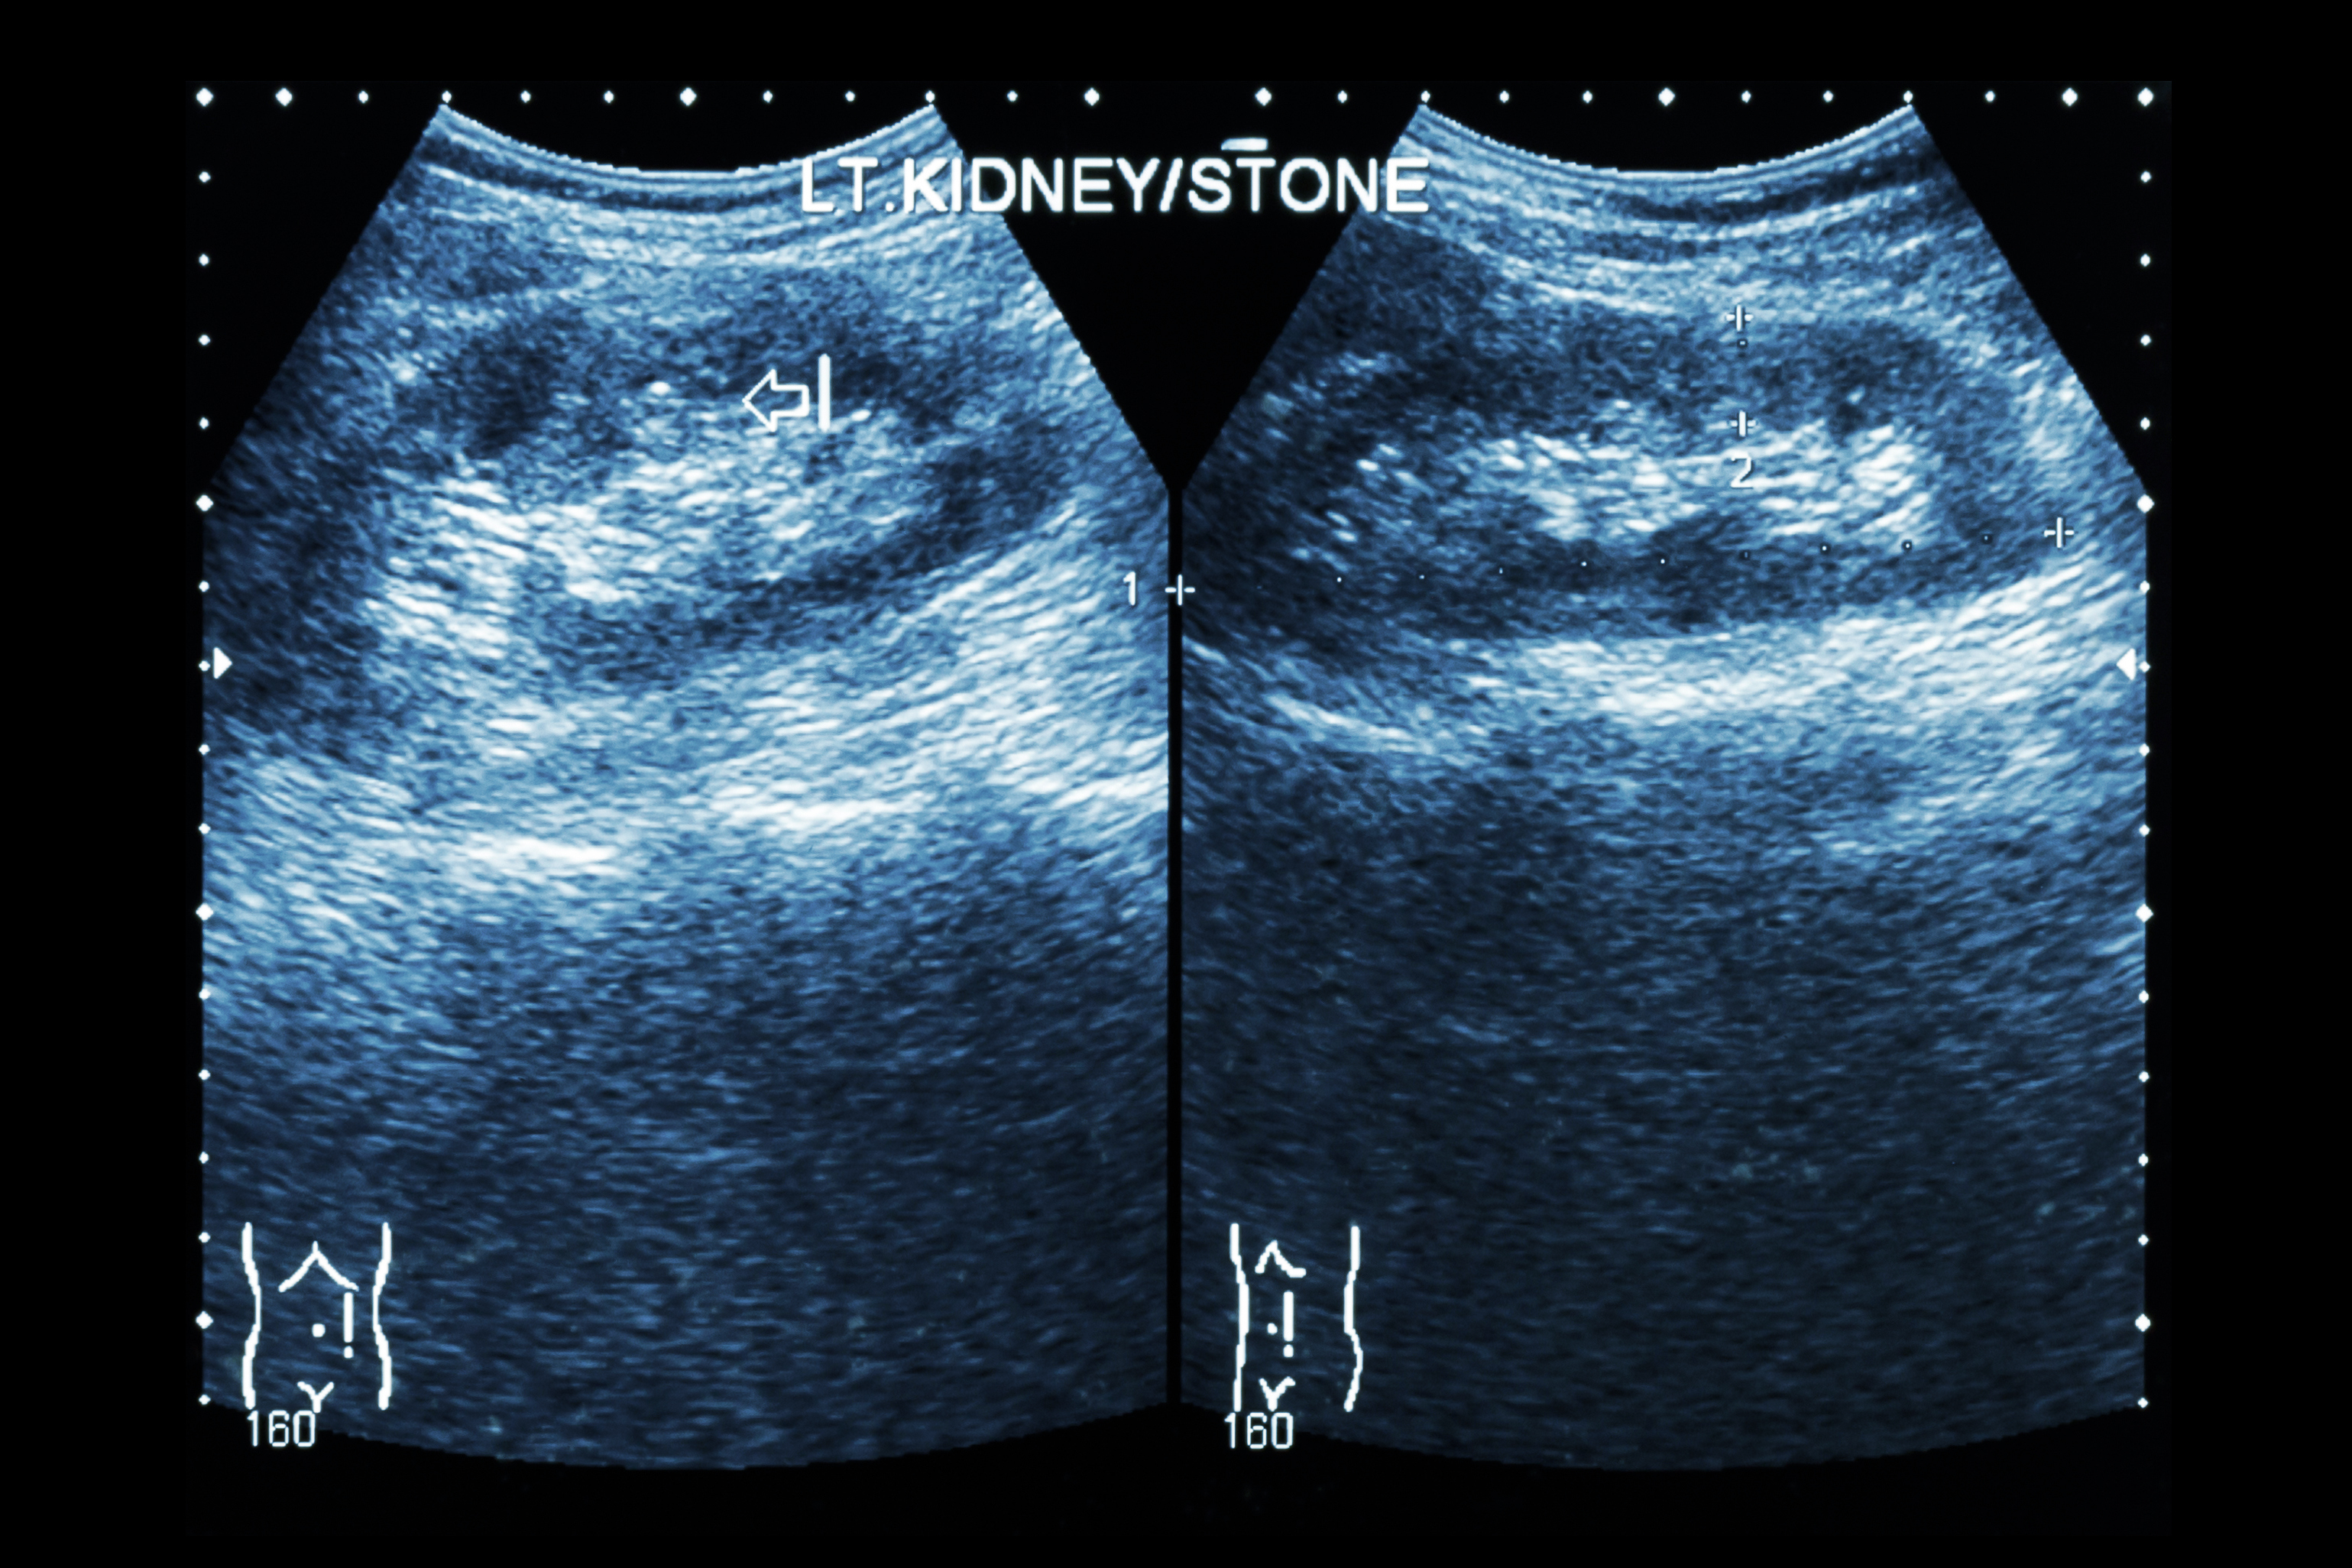

Recurrent kidney stone patients are at a higher risk of heart disease and osteoporosis. The findings suggest that close monitoring of recurring kidney stones could help protect patients from heart-related problems. Nearly 10 percent of men and seven percent of women will develop kidney stones, and over the last few decades mounting evidence has shown ...click here to read more